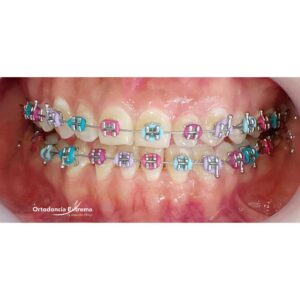

Los brackets metálicos son la opción clásica, resistente y efectiva. El mercado es amplio: encuentras desde brackets alemanes de alta tecnología, que ofrecen máxima precisión, hasta opciones chinas de bajo costo. La calidad del bracket influye en tu resultado.